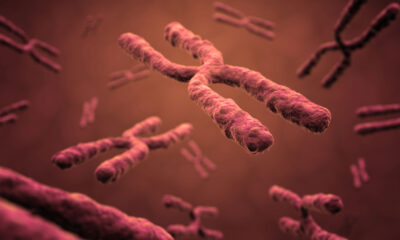

Renovatio 21 riprende brani di questo articolo di Bioedge. Quando dovrebbero gli scienziati procedere con l’ingegneria genetica ereditaria? Il dottor He Jiankui, cinese, ha scelto il...